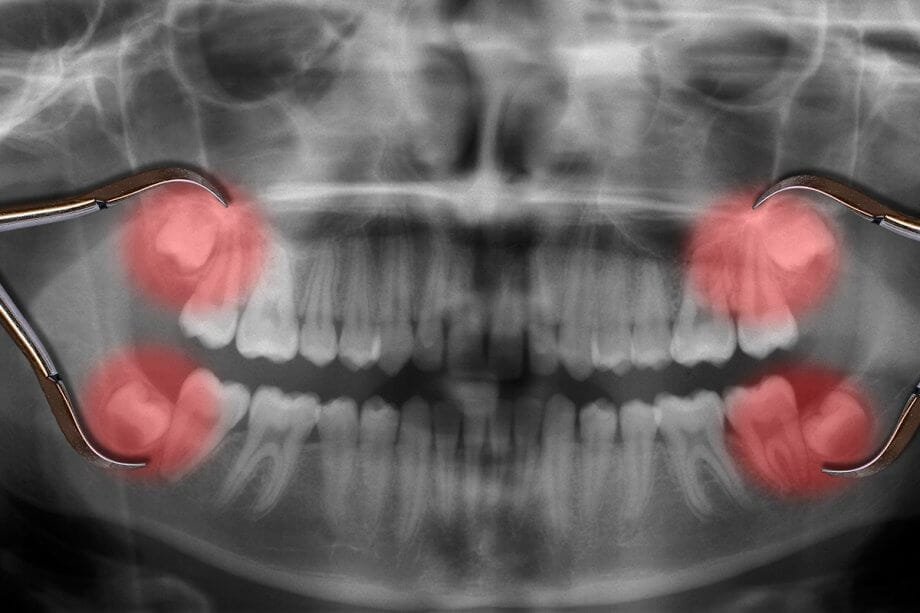

একটি আত্মবিশ্বাসপূর্ণ হাসি আপনার জীবন বদলে দিতে পারে। কিন্তু যদি দাঁতের অভাব আপনাকে পিছনে টানে? তাহলে, ডেন্টাল ইমপ্ল্যান্ট এর মাধ্যমে আপনার হারিয়ে যাওয়া হাসিকে ফিরে পান। ডেন্টাল ইমপ্লান্ট হল একটি স্থায়ী এবং প্রাকৃতিক সমাধান যা হারিয়ে যাওয়া দাঁত প্রতিস্থাপনের জন্য ব্যবহৃত হয়। ডাঃ অনুরাধা বোস ডেন্টাল ক্লিনিকে, আমরা আপনাকে আরামদায়ক,দীর্ঘস্থায়ীএবং উন্নত ডেন্টাল ইমপ্লান্ট চিকিৎসা প্রদান […]